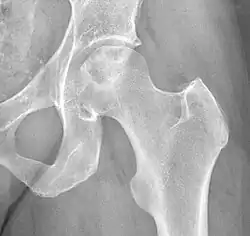

Chandler's disease, also known as idiopathic avascular osteonecrosis of the femoral head (ANFH or ONFH), is a rare condition in which the bone cells in the head of the femur (FH) die due to lack of blood. This disease is caused when blood flow is reduced to the part of a bone near a joint. It is specifically unique because the femoral head is for some reason the only affected part of the body and rarely travels down to the main part of the femur. In 1948, F. A. Chandler did a multi-case review and first released his interpretations as Coronary Disease of the Hip. This term is now considered incorrect as it improperly describes the actual disease.[1]